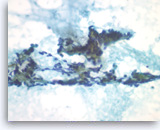

Non-Hodgkin B-cell lymphoma,

Pancreas FNA, Cell Block.

Atypical lymphoid infiltrates are present in fibrotic tissue fragment. The atypical cells are intermediate to large in size and have irregular nuclear contours and conspicuous nucleoli. Flow cytometry of the aspirates demonstrates a monoclonal B-cell lymphoma. Overall, the findings are consistent with diffuse large B-cell lymphoma.

40X

Non-Hodgkin B-cell lymphoma,

Pancreas FNA, Cell Block.

Atypical lymphoid infiltrates are present in fibrotic tissue fragment. The atypical cells are intermediate to large in size and have irregular nuclear contours and conspicuous nucleoli. Flow cytometry of the aspirates demonstrates a monoclonal B-cell lymphoma. Overall, the findings are consistent with diffuse large B-cell lymphoma.

40X